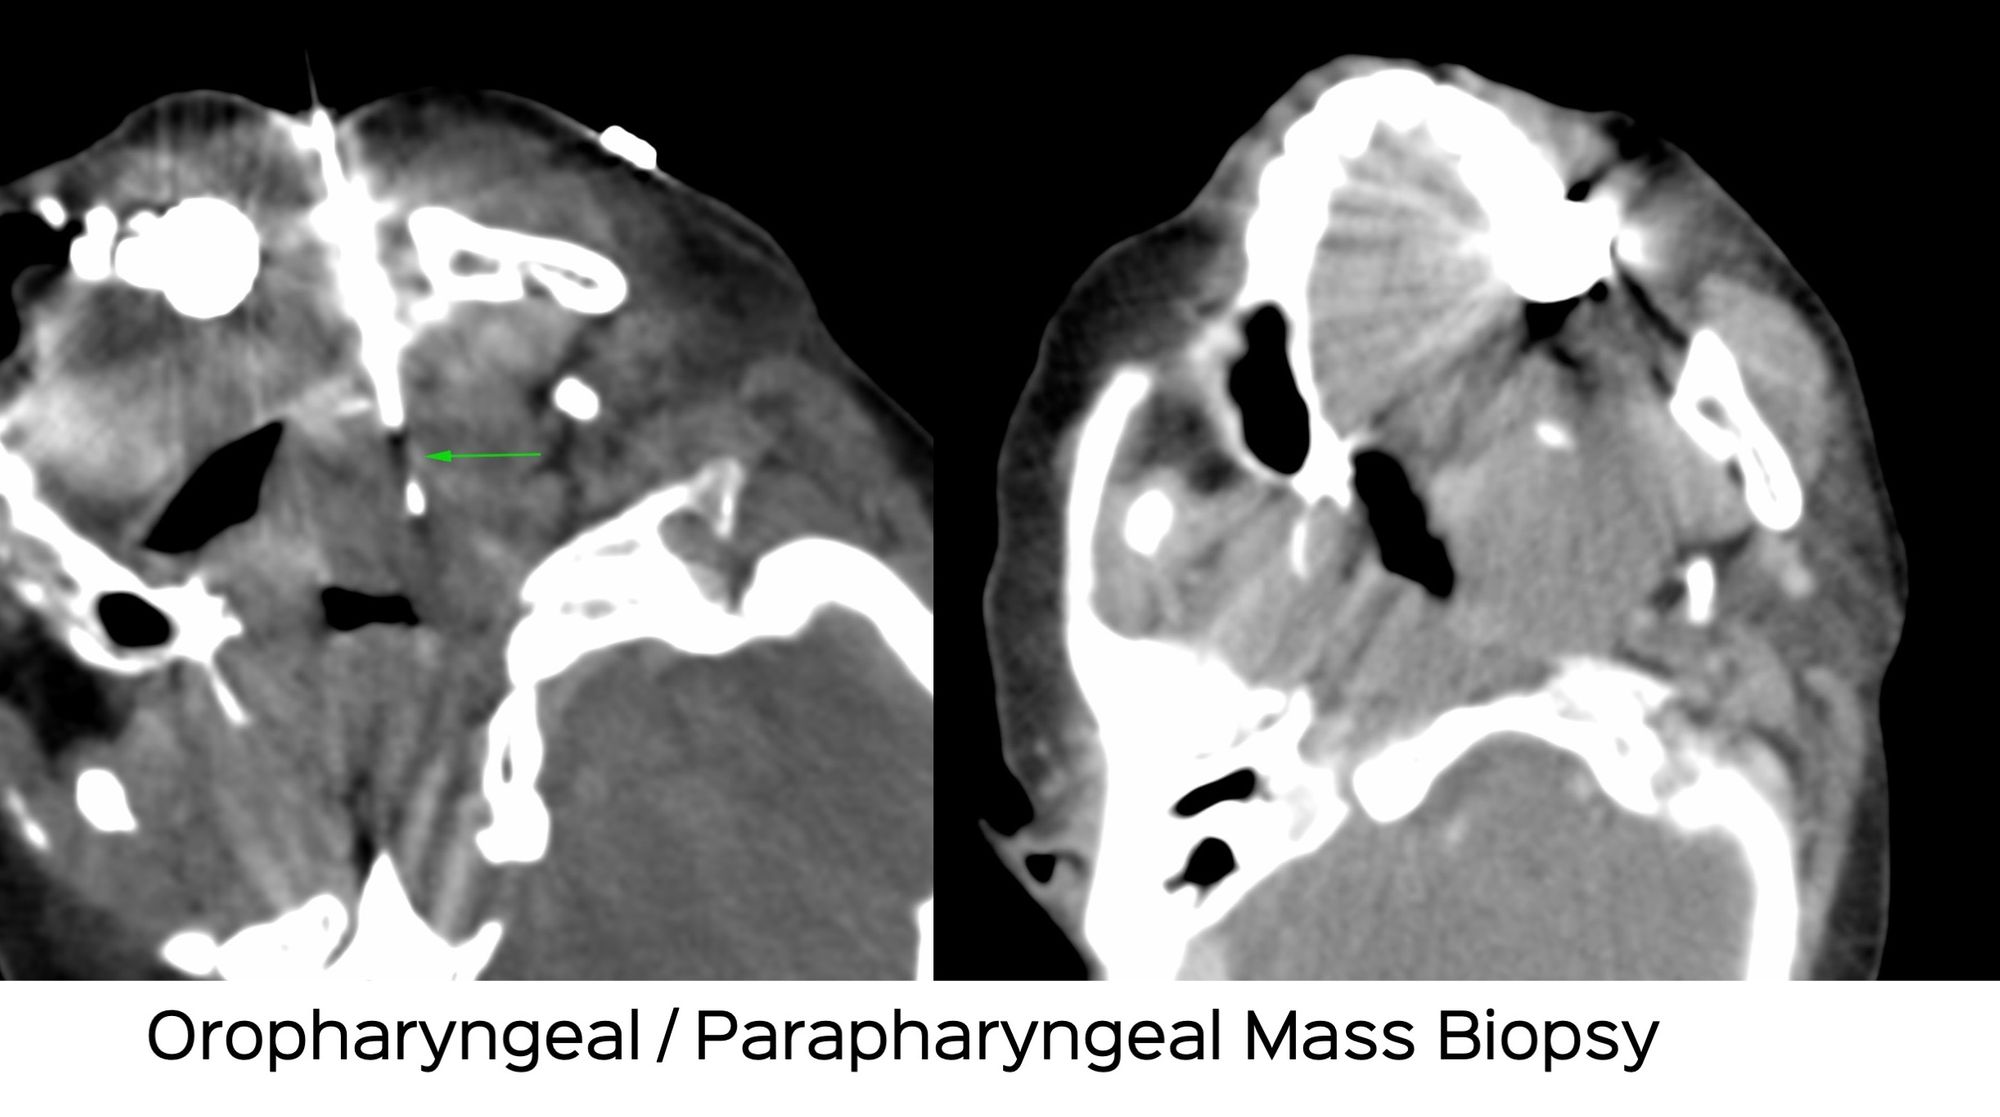

Case 24: Oropharyngeal / Parapharyngeal Mass Biopsy

Bhavin Jankharia - 18 April 2021